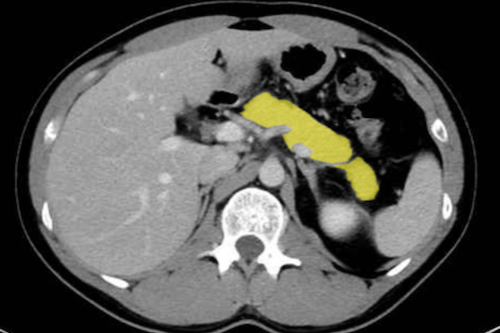

췌장 질환

췌장은 위치상 초음파 관찰이 어려운 장기로, CT의 진단 가치가 매우 큽니다.

- 췌장암: 종괴 존재, 혈관 침범 및 전이 여부

- 췌장 낭성 종양: 낭종 형태의 병변 구분